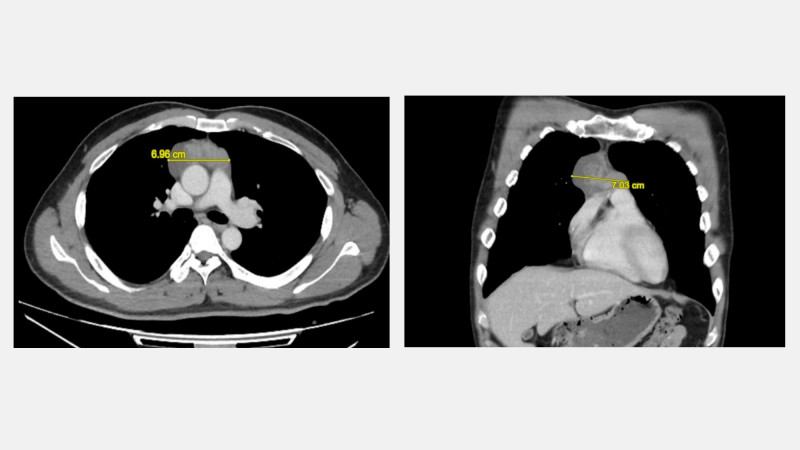

6旬男7cm胸腺瘤 動達文西手術僅3cm傷口

〔記者陳建志/台中報導〕68歲陳先生日前接受國民健康署補助的低劑量胸部電腦斷層掃描,意外發現縱膈腔內有一顆約7公分的腫瘤,雖未出現任何胸悶、咳嗽等症狀,但醫師研判可能是胸腺瘤,若不及時處理,恐會壓迫心臟、氣管或其他器官,胸腔及心臟血管外科醫師決定以健保給付的達文西機器人手術系統精準切除胸腺瘤,讓他順利康復,重拾健康生活。